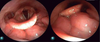

Qual o nível e a configuração da obstrução segundo o VOTE e NOHL?

Fechamento concêntrico em velofaringe (V pela VOTE) ou orofaringe (O, pela NOHL).